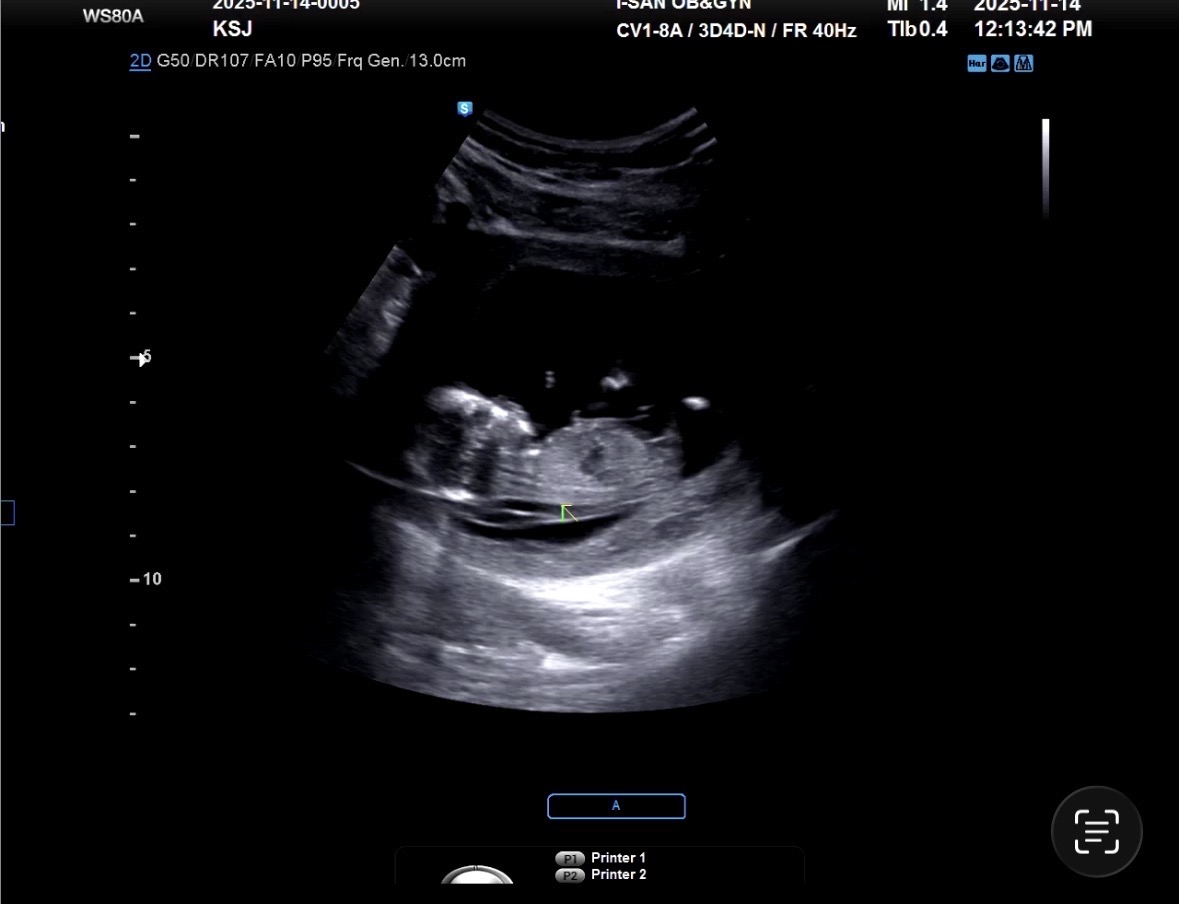

12주차 각도법 궁금해요!!!

각도법 잘보시는분!! 투표해주시면 감사합니다 🥹